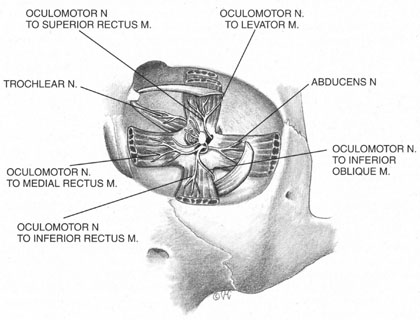

The motor supply of the superior, medial, and inferior rectus, the inferior oblique, and the levator palpebrae superioris is carried by the oculomotor nerve (Fig. 2). It also carries proprioceptive input from these muscles and parasympathetic fibers to the ciliary ganglion. As the oculomotor nerve enters the orbit through the superior orbital fissure, it splits into two divisions, superior and inferior. The superior division is smaller; it courses forward in the superolateral portion of the intraconal space, and turns medially toward the lateral aspect of the superior rectus muscle, where it divides into a network of small branches.49 The innervation of all extraocular muscles is multifocal, with nerve fibers extending distally and proximally between the muscle fibers, before ending at myoneural junctions.47 Some branches innervate the superior rectus, and others pass through it to enter the levator muscle through its inferior surface.

The inferior division of the oculomotor nerve splits into at least three trunks within the intraconal space, and these in turn divide into eight to ten branches as they course forward, lateral to the optic nerve. The medial rectus is innervated by branches that run from beneath the optic nerve into the muscle, beginning at its posterior third. The inferior rectus muscle is similarly penetrated at its posterior conal surface by branches of the inferior division of the oculomotor nerve. The inferior oblique muscle is innervated by a branch that initially contains parasympathetic fibers; these fibers originate in the Edinger-Westphal nucleus and enter the ciliary ganglion inferolateral to the optic nerve. The remainder of this branch then breaks up into smaller fascicles, which penetrate the inferior oblique at its posterolateral aspect.47

The trochlear nerve supplies motor fibers to the superior oblique muscle. It enters the orbit through the superior oblique fissure above the annulus of Zinn, along with the frontal and lacrimal branches of the ophthalmic division of the trigeminal nerve. It crosses the superior rectus origin above the levator and enters the superolateral surface of the superior oblique muscle.47

The abducens nerve enters the orbit through the superior orbital fissure, along with the oculomotor nerve. They are sometimes divided by a dense septum connecting the superior rectus origin to the superior rectus sheath.47 The abducens nerve enters the lateral rectus sheath just anterior to the annulus of Zinn, and first enters the lateral rectus muscle at the medial aspect of the junction of its posterior and medial thirds.47,50